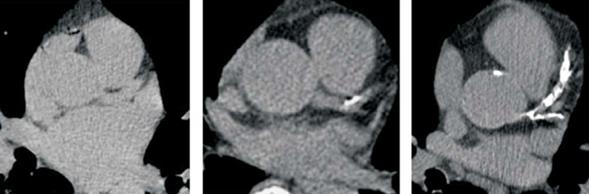

Como veremos más adelante, y con un criterio pronóstico, se ha categorizado el SCC: score 0 implica la ausencia de placas calcificadas, 1-10 UA placas calcificadas mínimas, 11-100 UA calcificación leve, 101-300 UA calcificación moderada y > 300 UA calcificación coronaria severa4. Otros trabajos consideran como calcificación coronaria severa cuando el SCC > 400 UA5. Ejemplos de diferentes categorías se muestran en la (figura 2).

Figura 2: Ejemplos de diferentes grados de score de calcio coronario: a la izquierda, ausencia de placas calcificadas (score 0). En el centro, score de calcio < 100 UA, con placa calcificada en el inicio de la arteria descendente anterior. A la derecha, score de calcio > 300 UA, con placas calcificadas a nivel de tronco de coronaria izquierda, descendente anterior y circunfleja.